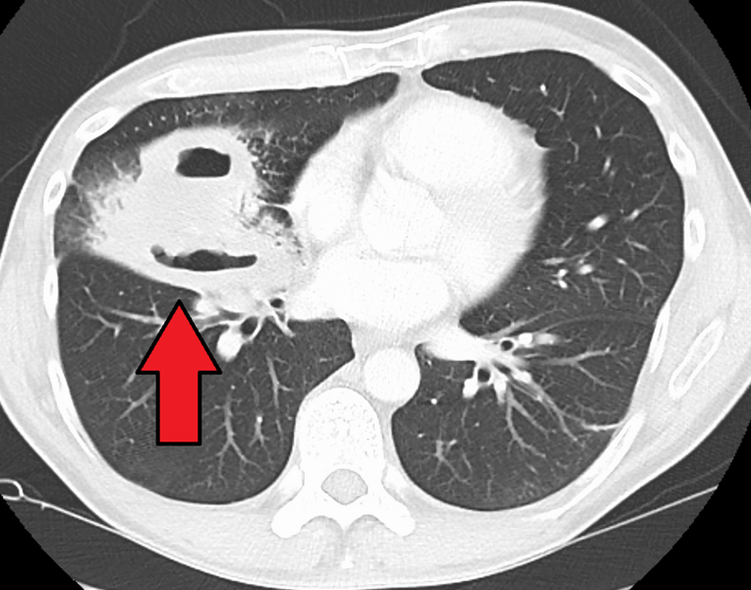

2) CXR: Air-fluid level이 보이는 두꺼운 벽의 공동(thick-walled cavity)

3) CT: CXR과 동일 / 농흉(empyema)와의 감별에 도움